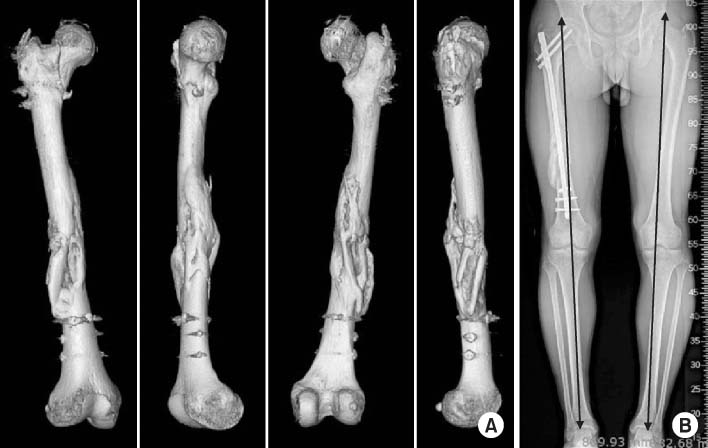

Fig. 1

(A) Three-dimensional-reconstructed computed tomography image shows a fragmented wedge fracture at the femur shaft infraisthmal area. (B) Intra-operative C-arm images show the sequence of Poller screw insertion. (C) Postoperative radiograph shows a well reduced femur with good positioned Poller screws.

Fig. 1 (A) Three-dimensional-reconstructed computed tomography image shows a fragmented wedge fracture at the femur shaft infraisthmal area. (B) Intra-operative C-arm images show the sequence of Poller screw insertion. (C) Postoperative radiograph shows a well reduced femur with good positioned Poller screws.